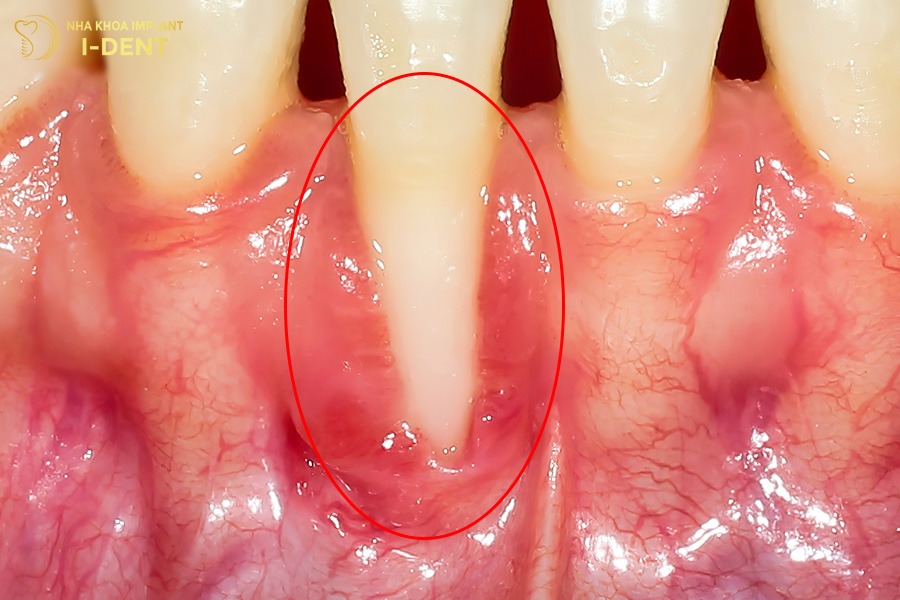

1.1. Bị viêm nướu, nhiễm trùng nướu

Trong quá trình niềng răng, viêm nướu là tác hại phổ biến nhất và thường xuất hiện sớm. Nguyên nhân chủ yếu đến từ việc hệ thống mắc cài và dây cung tạo ra nhiều khe kẽ khiến mảng bám và thức ăn dễ tích tụ. Khi vi khuẩn phát triển mạnh, nướu bị kích ứng, sưng đỏ, dễ chảy máu và nếu kéo dài có thể tiến triển thành viêm nha chu. Tình trạng này không những làm ảnh hưởng đến mô mềm mà còn gây tiêu xương ổ răng, làm giảm độ vững chắc của răng trong quá trình chỉnh nha.

Sau khi niềng răng nếu không vệ sinh đúng cách có thể gây viêm nướu.